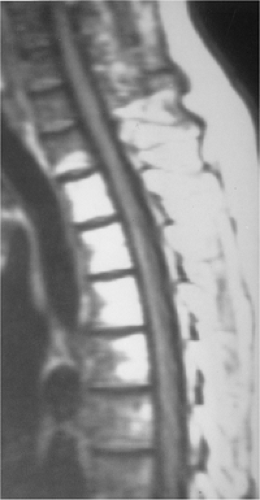

fba59273f7a0d4393edd5a753f4207d2.png

(A) 六个月前,胸椎矢状位 T2 加权 MRI 显示 T9 和 T12 急性压缩性骨折。

(B) 椎体后凸成形术后,腰椎矢状位 T2 MRI 显示 T8 、 T10 和 T11 处急性压缩性骨折,T9和 T12 处有明显的骨折线。